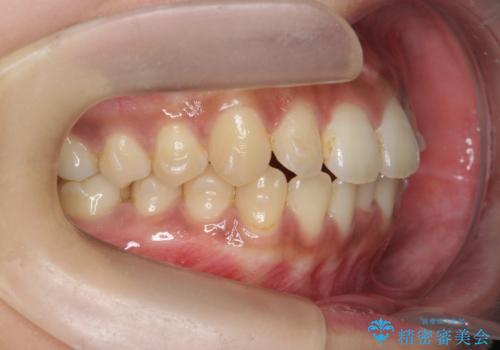

前歯のがたつきをすっきり マウスピース矯正

- 長年気になっていた前歯のがたつきをマウスピース矯正で治したい!と希望され来院されました。

奥歯の噛み合わせには問題がなく、前歯のがたつきの改善のみで十分に審美的な結果が得られるため、ワイヤーではなくマウスピース矯正での治療を計画します。

しっかりと前歯のがたつきは改善し見た目が大きく良くすることができました。